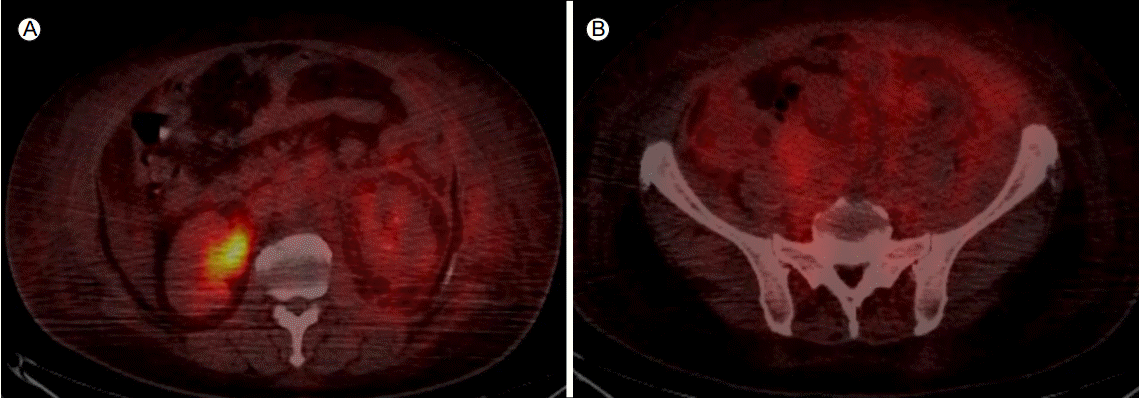

Figure 3.

Positron emission tomography-computed tomography showed diffuse fludeoxyglucose uptake in the retroperitoneum (A) and the pelvic cavity (B).